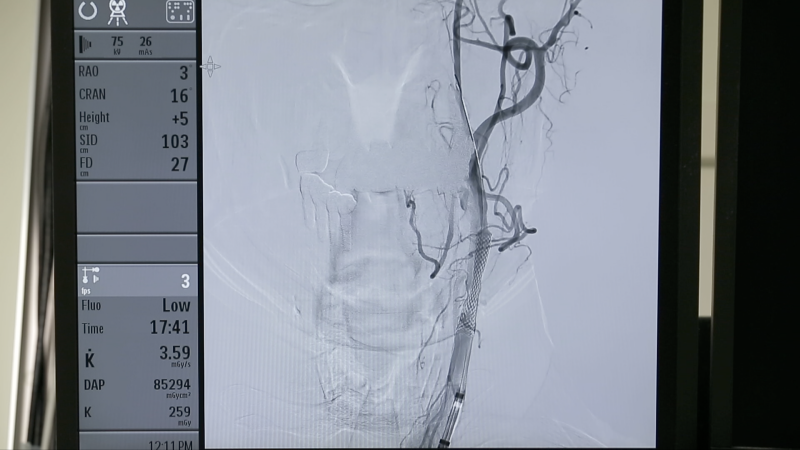

뇌 혈류 검사 목적으로 병원에 방문했다가 동맥경화로 인한 경동맥 협착을 발견한 70대 후반의 한 남성. 평소 별다른 증상을 느끼지 못했지만, 경동맥 협착이 80% 이상 진행된 상태! 뇌로 가는 혈액을 공급하는 경동맥에 협착이 일어날 경우 뇌경색 발병률도 높아진다. 게다가 경동맥의 혈전이 뇌로 날아갈 경우 더 큰 위험에 빠질 수 있다. 김동준 교수는 이 문제를 해결하기 위해 경동맥에 스텐트를 삽입하는 시술을 시행했다. 외과적 수술인 경동맥 내막절제술을 시행할 수도 있지만 나이와 증상 유무를 고려해 뇌경색 예방을 위한 치료 목적으로 뉴로인터벤션을 선택했다.